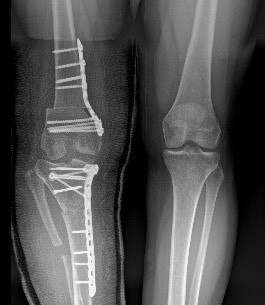

Osteotomy: Cutting and realigning bones

Deformity Correction: Correcting angular or rotational abnormalities for better function and appearance

Advanced surgical techniques like Ilizarov fixators and modern osteotomies